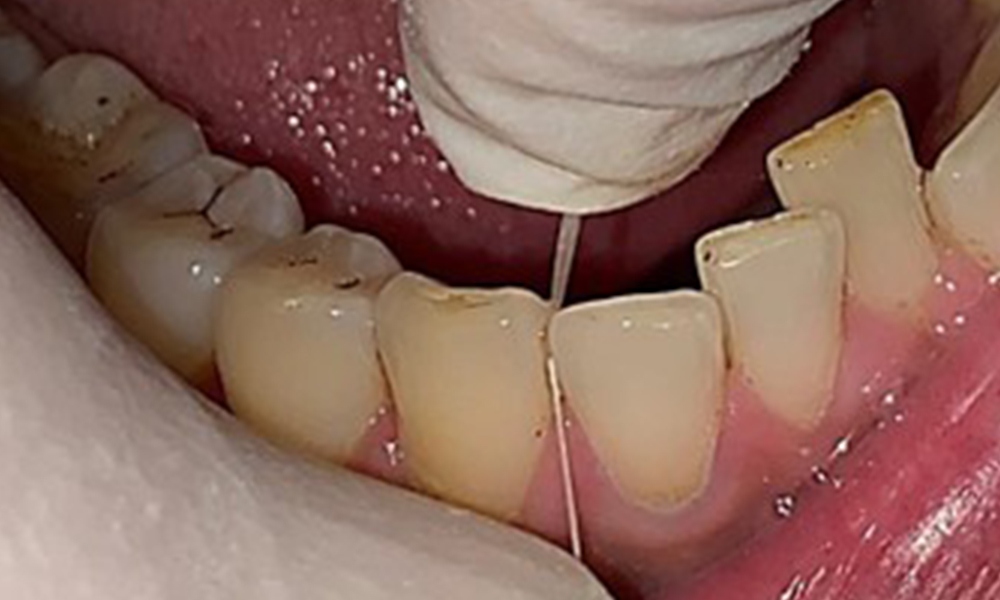

Résultats dentaires

Le patient a une dentition complète avec un total de 28 dents. Il y avait des érosions et des attritions notables. (Fig. 4, Fig. 5). En raison du bruxisme, le patient a porté pendant de nombreuses années une attelle avec une gouttière ajustée la nuit. Les érosions ont été causées par une consommation prolongée de boissons isotoniques. Aucune perte d'os parodontal ou carie active n'a été observée.